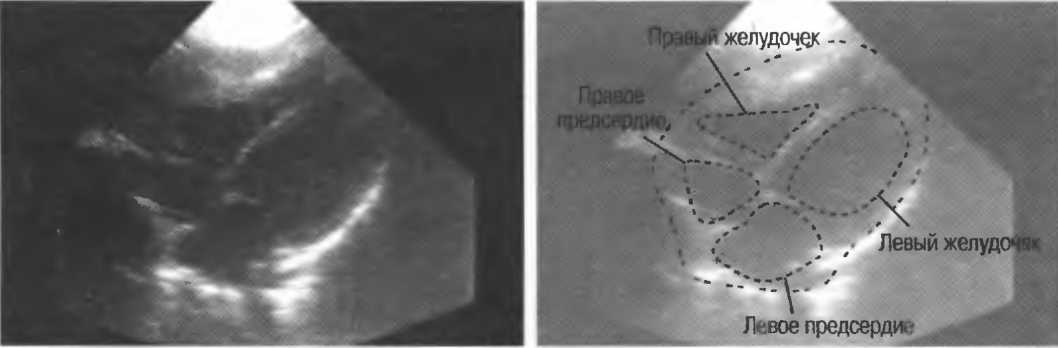

4. Режим дуплексного доплеровского сканирования. Кровеносный сосуд изображается в В-режиме, скорость кровотока определяется доплерографически. Такое сочетание В-режима и доплерографии позволяет более точно получить информацию с данного конкретного сосуда (рис. 2в,г).